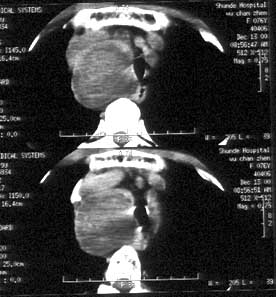

ΓΓΓΓΝΌ¥≤…œΦΉΉ¥œΌΫαΫΎΒψΉ¥ΗΤΜ·”κΦΉΉ¥œΌΑ©”–“ΜΕ®ΒΡΙΊœΒΓΘ“ΜΑψΦΉΉ¥œΌΫαΫΎ‘Φ”–25%≥ωœ÷ΗΤΜ·“θ”ΑΘ§ΕχΦΉΉ¥œΌΑ©‘ρ”–50%ΓΪ62.5%”–ΗΤΜ·ΓΘ“ΜΑψ»œΈΣΗΤΜ·Ω≈ΝΘ‘Ϋ¥÷¥σΘ§Α©Ήι÷·Ζ÷Μ·‘ΫΚΟΓΘ![]() ”κ“Ϋ…ζœξœΗΙΒΆ®≤Γ«ιΘ§―Α’“ΫœΚΟ÷ΈΝΤΖΫΑΗΓΘ

ΓΓΓΓ3ΓΔ÷ΉΝωΚή¥σΘ§≥ωœ÷ΝΥ―ΙΤ»ΓΔ…υ“τΥΜ―ΤΓΔΆΧ― άßΡ―Θ§…θ÷Ν”–ΒΡ÷ΉΝωΟςœ‘”ΑœλΒΫΝΥΚτΈϋΓΘ![]() ΈςΑ≤–¬≥«÷–¥σΕ汫Κμ“Ϋ‘Κ‘Ύ÷ΈΝΤΦΉΉ¥œΌΦ≤≤Γ…œΘ§ΦΦ θ–ßΙϊΖΫΟφ”–ΡΡ–©”≈ Τ——